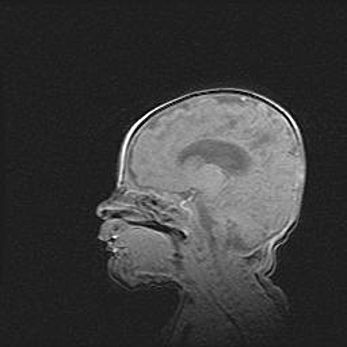

Лейкомаляция с кистозно-глиозной дегенерацией головного мозга.

Возраст: 2 месяца 25 дней

Вес: 6400 г

Окружность головы: 40 см

Срок гестации: 41 неделя

Лейкомаляцию относят к ишемически-гипоксическим повреждениям головного мозга, диагностируемым у новорожденных. При лейкомаляции в головном мозге обнаруживают очаги некроза, возникшие после тяжелой гипоксии и нарушения кровотока. В процессе морфогенеза очаги проходят три стадии: 1) развития некроза, 2) резорбции и 3) формирования глиозного рубца или кисты. Перивентрикулярная лейкомаляция (ПЛ) встречается примерно в 12% случаев среди новорожденных, обычно – у недоношенных детей, причем, частота ее зависит от массы, с которой младенец появился на свет. Наибольшее число малышей страдает лейкомаляцией, если масса при рождении 1500-2500 г.